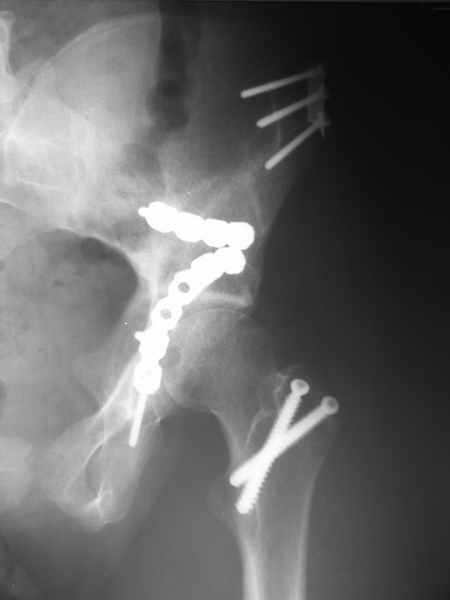

1 закрытая репозиция аппаратом + фиксация через проколы винтами

2 закрытая репозиция передней колонны + открытая задней колонны из задне-неружного доступа

3 открытая репозиция передней колонны из подвздошнго доступа + открытая задней колонны из задне-наружного доступа

4 открытая репозиция из илиоингвинального доступа

5 открытая репозиция из Y образного доступа

Я бы ориентировался на Y образный доступ

или из двух если есть сомнения в целостности задних отделов крыла.

прикладываю схему доступа и случай.

Одним задне наружным переднюю колонну не достать, а илио-ингвинальный более сложный не позволяет контролировать суставную поверхность и трудно управлять задней колонной.